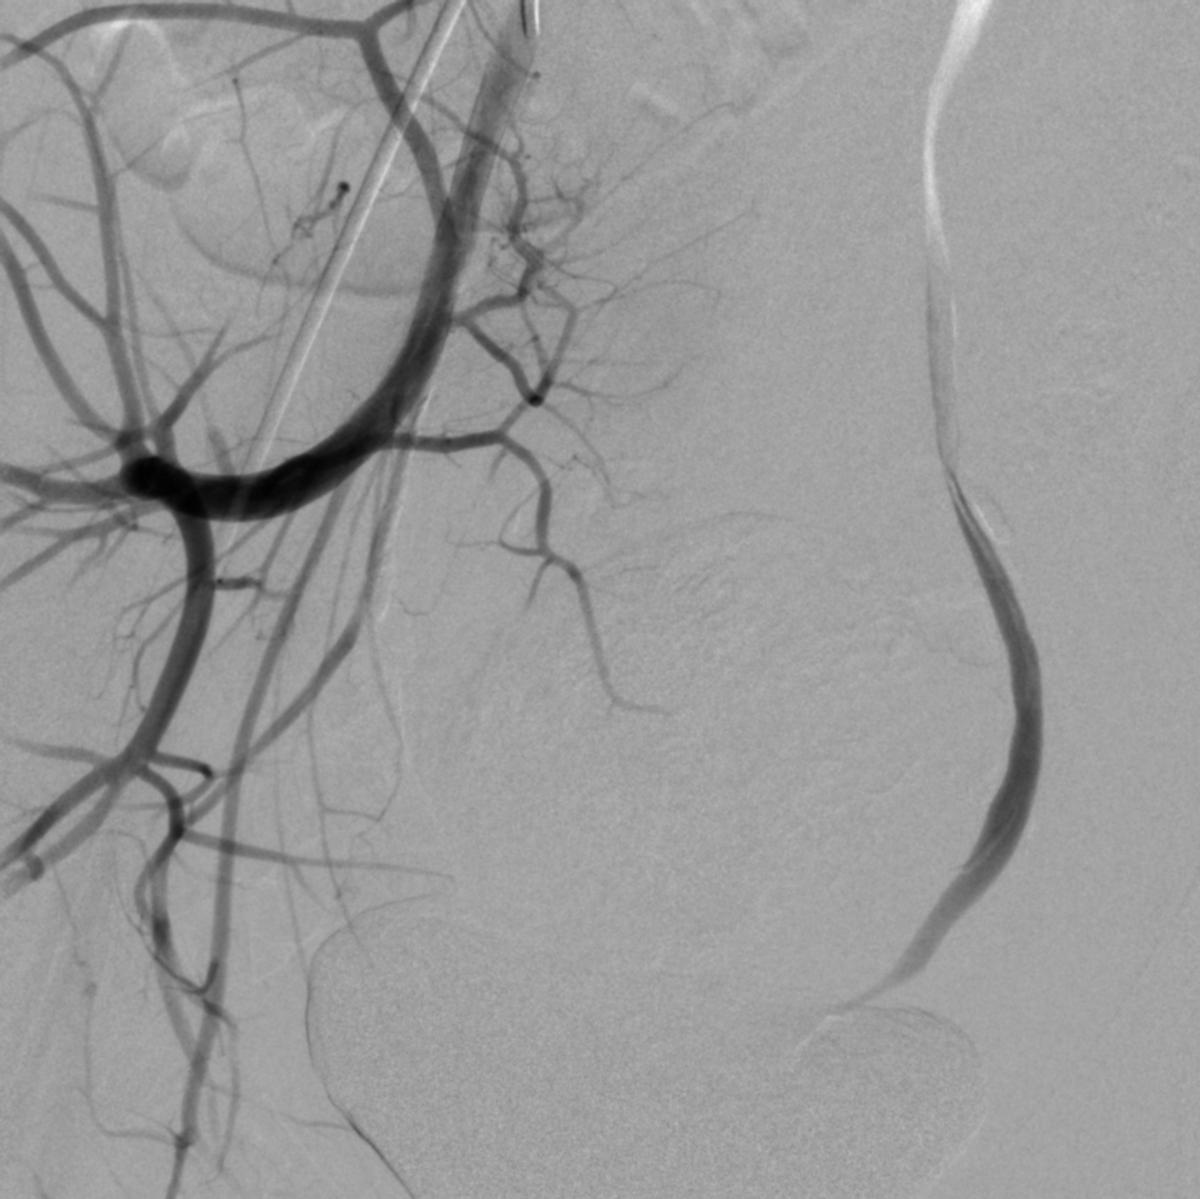

患儿完成入院前术前检查,并进行了全科的术前讨论。结合患儿体征及相关的术前检查,目*考前**虑PROS综合症。目前主要解决的是月经出血的问题,可以通过栓塞双侧子宫动脉来进行治疗。患儿全麻后,使用5F穿刺针行右股动脉穿刺,成功后置入5F血管鞘,导丝引导下置入5F Headhunter Angiopointer造影导管,在导丝引导下选入髂内动脉,进入子宫动脉,造影见左侧子宫动脉远端纤细,右侧子宫动脉螺旋增粗,微导丝引入微导管进入子宫动脉,使用聚乙烯醇颗粒栓塞剂350um-560um,栓塞微粒球(300-500um)分别行双侧子宫动脉栓塞,栓塞后造影未见子宫动脉远端分支显影。

右侧子宫动脉造影